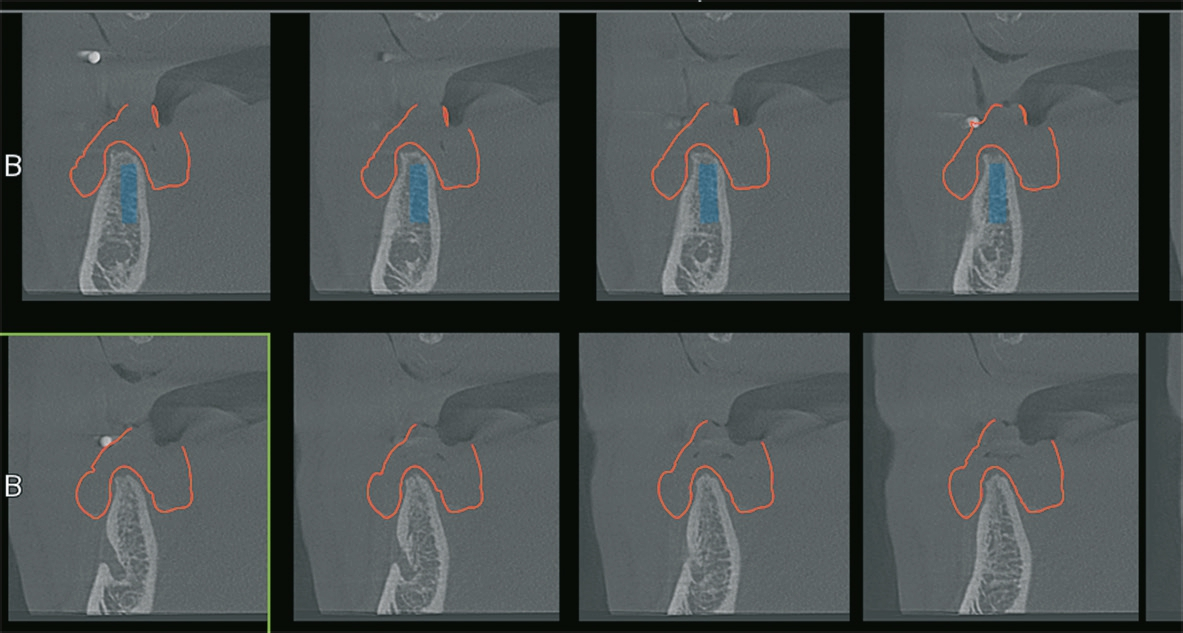

Im vorgestellten Fall wurde die Planung über eine externe Software durchgeführt, die dann von der Firma C-Tech (Italien) übernommen wurde. Für den Patienten wurden im Vorfeld Prothesen hergestellt, welche im DVT mit eingebracht wurden, um eine entsprechende Planung der Soll-Position durchführen zu können.

Die Abbildungen 1 bis 3 zeigen die Ausgangssituation. Zuerst wurde nach der Herstellung einer Prothese eine Implantatplanung gemacht. In den Abbildungen 5 bis 7 zeigt sich die Herausforderung in diesem Fall: Geringe Platzverhältnisse für die Implantate im Knochen. Nachdem die erstellten Daten verschickt wurden, bekommen wir die Schablonen zurück (Abb. 8).

Die digitale Planung der Implantatposition hat sich als vorteilhaft herausgestellt. Denn meistens geht mit der digitalen Planung der Implantatposition eine geringere Augmentationsnotwendigkeit einher. Die Implantate werden optimaler in den vorhandenen Knochen gesetzt, da alle Informationen über den Knochenbedarf als auch die Positionierung in Bezug auf den Zahnersatz bekannt sind. Auch werden die Implantate nicht einzeln, sondern alle gemeinsam zueinander im Kiefer ausgerichtet.